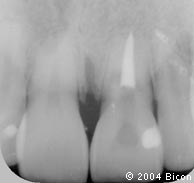

3. | 术前的X光片显示上颌中切牙的根管治疗失败。 |